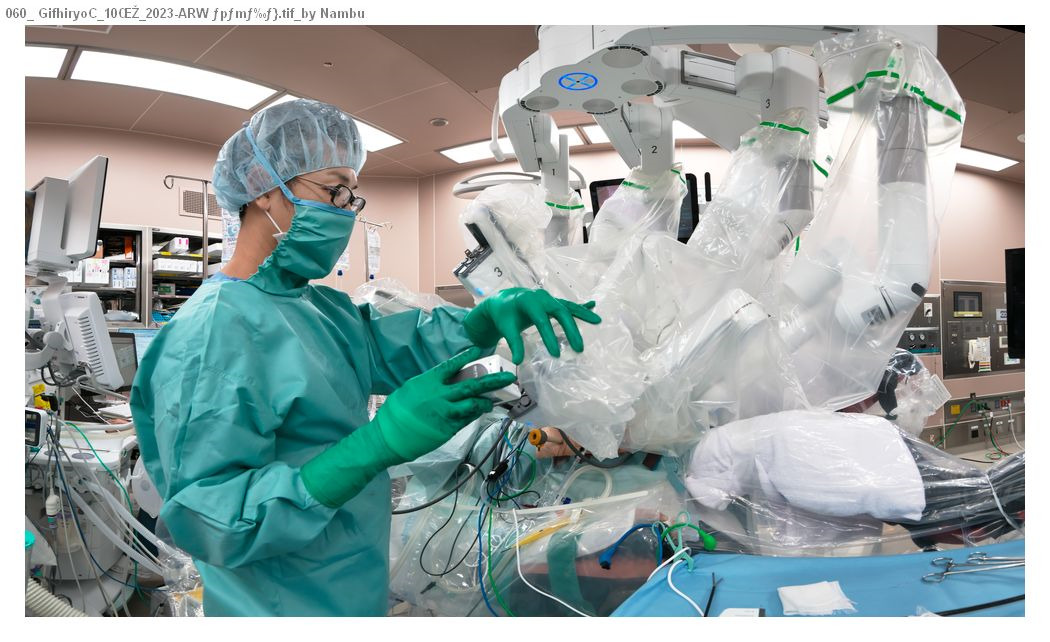

以前は開腹手術が行われていましたが、現在では小さな手術創で体にやさしい腹腔鏡下手術やロボット支援下手術が主に行われるようになりました。これらの手術法により出血量の少ない精密な手術が可能になりました。美容的に優れているだけでなく、術後早期から食事が開始でき、早く退院できる(術後7~14日)ことや術後の腸閉塞が起こりにくいことなどの利点があります。

ロボット(ダビンチXi)支援下直腸切除術の実際